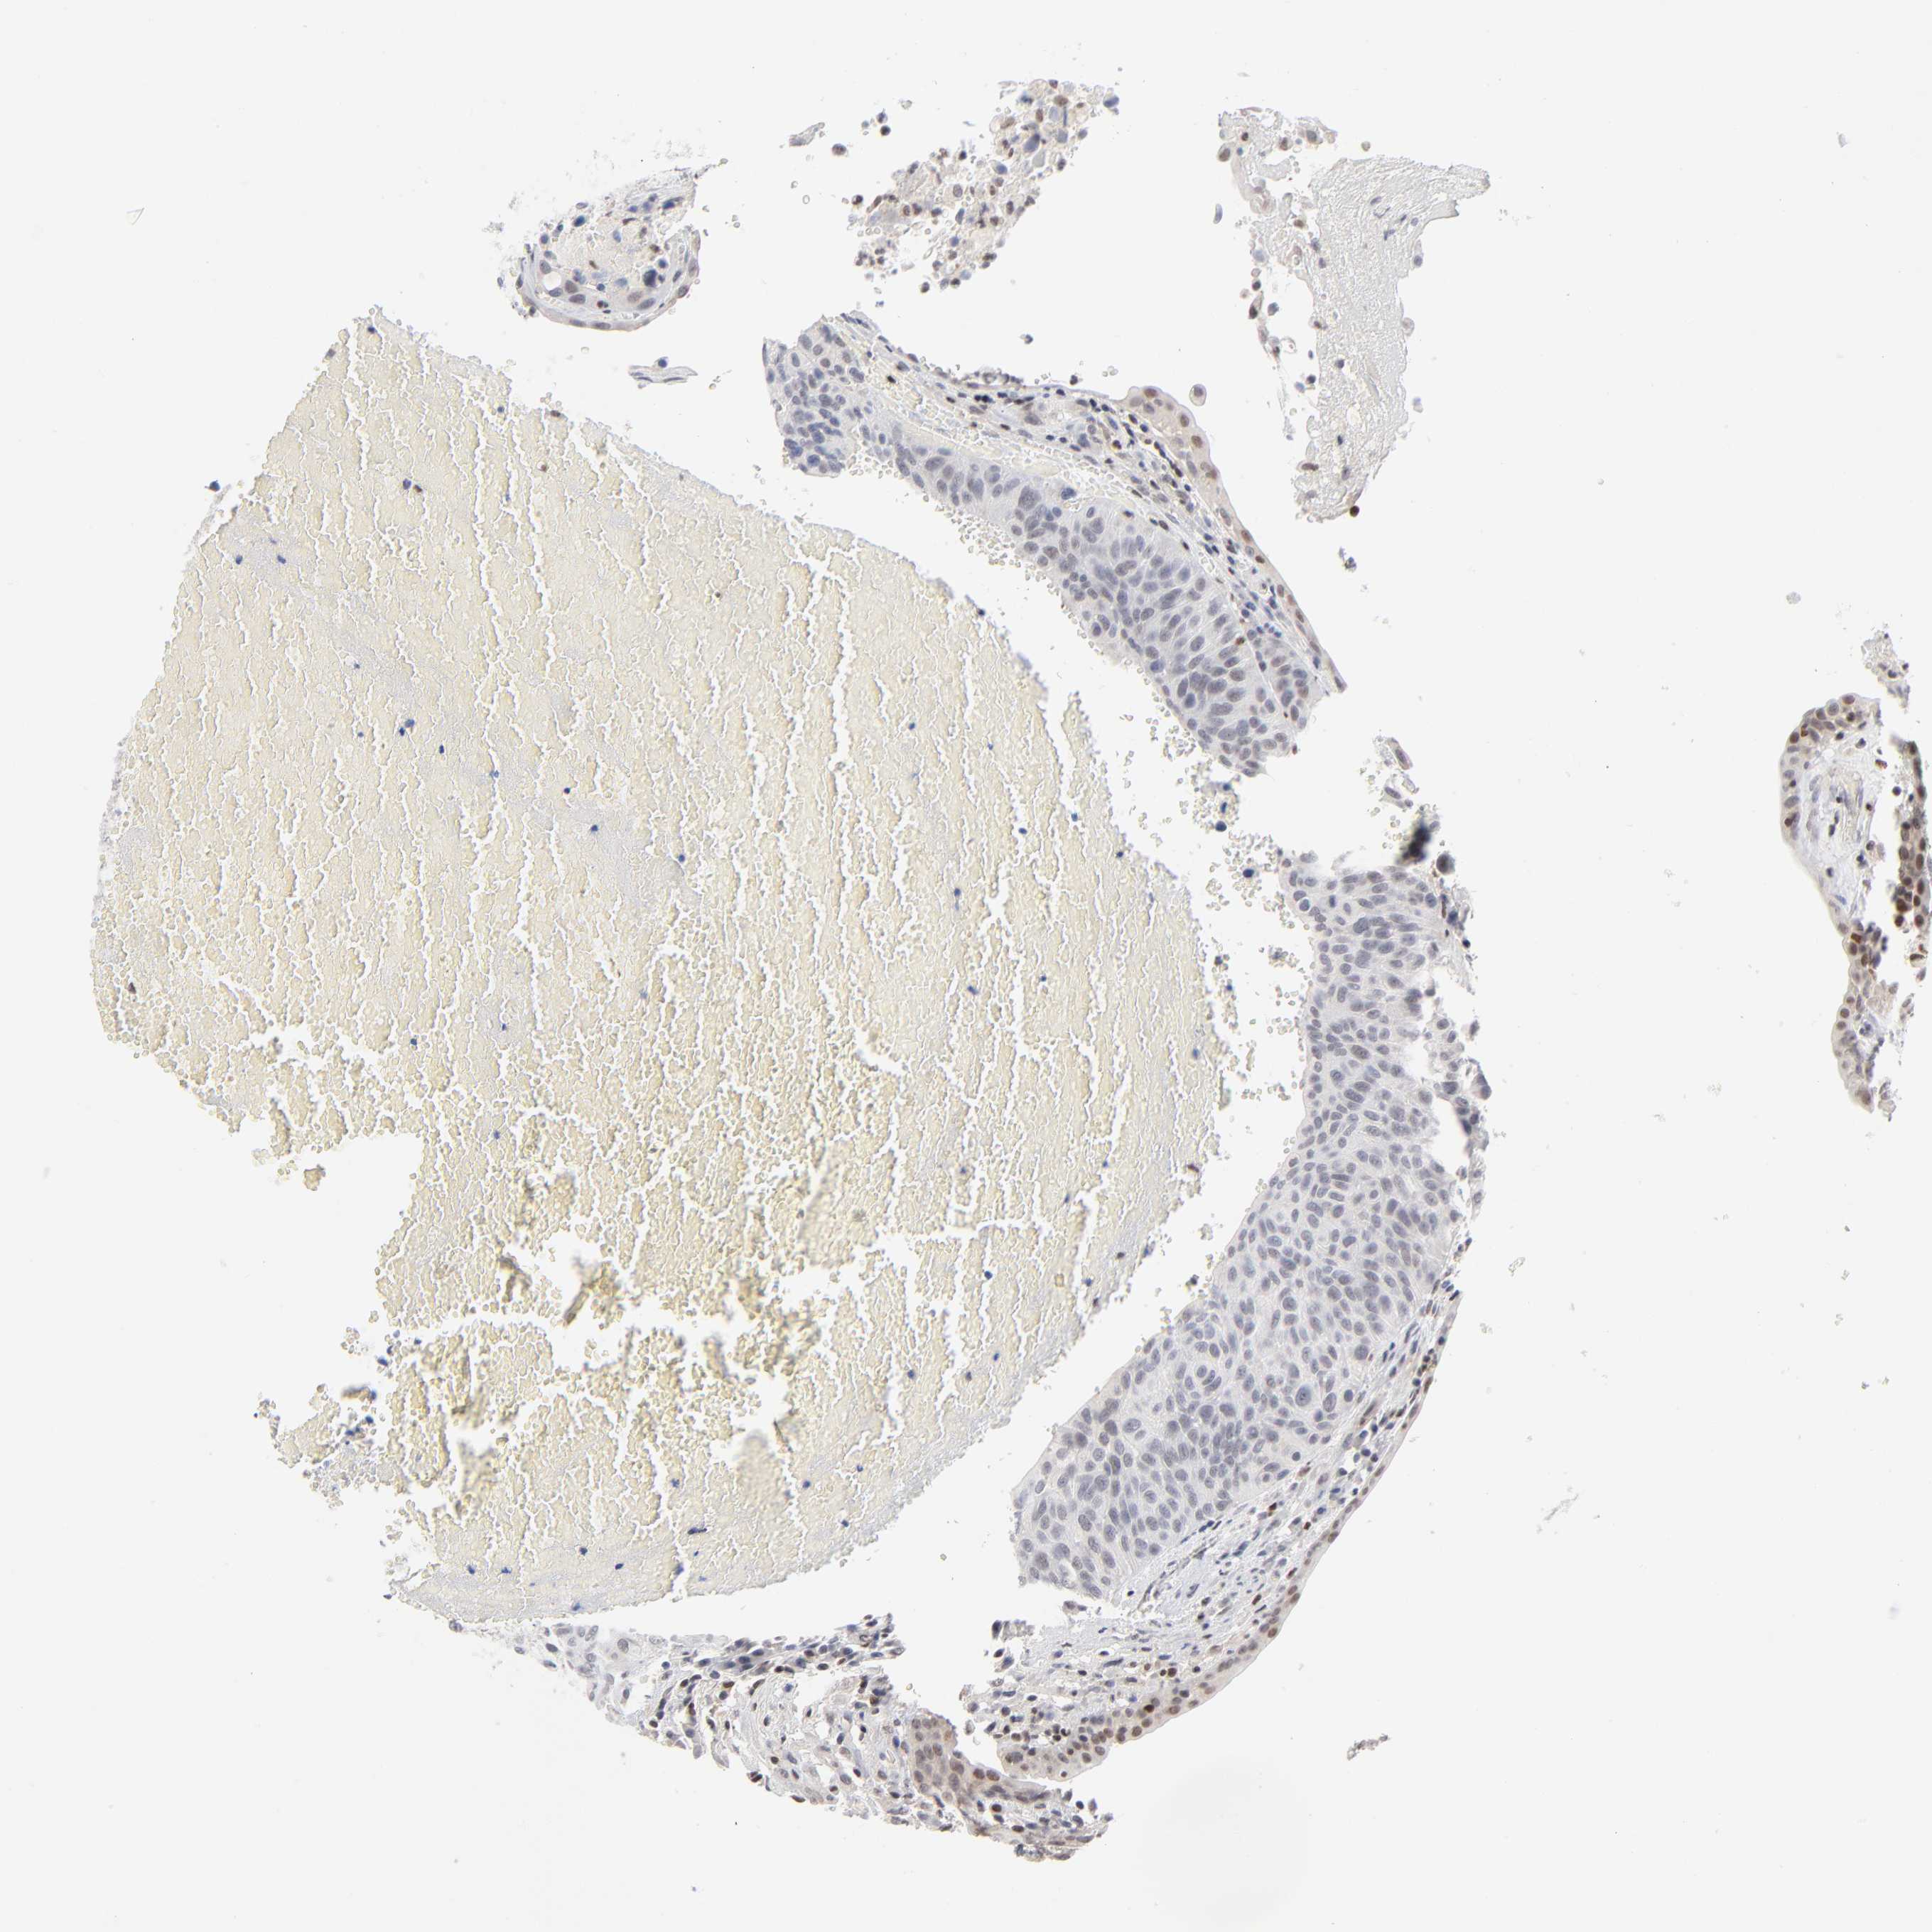

UROTHELIAL CANCER - Protein expressioni

A mouse-over function shows sample information and annotation data. Click on an image to view it in a full screen mode. Samples can be filtered based on level of antibody staining by selecting one or several of the following categories: high, medium, low and not detected. The assay and annotation is described here.

Note that samples used for immunohistochemistry by the Human Protein Atlas do not correspond to samples in the TCGA dataset.

Antibody stainingi

Antibody staining in the annotated cell types in the current human tissue is reported as not detected, low, medium, or high, based on conventional immunohistochemistry profiling in selected tissues. This score is based on the combination of the staining intensity and fraction of stained cells.

Each image is clickable and will lead to virtual microscopy that enables deeper exploration of all samples and also displays staining intensity scores, fraction scores and subcellular localization as well as patient and tissue information for each sample.

Antibody HPA003474

Antibody CAB000328

Staining

High

Medium

Low

Not detected

Intensity

Strong

Moderate

Weak

Negative

Quantity

>75%

75%-25%

<25%

None

Location

Nuclear

Cytoplasmic/membranous

Cytoplasmic/membranous,nuclear

Urothelial carcinoma, High grade

Urothelial carcinoma, Low grade